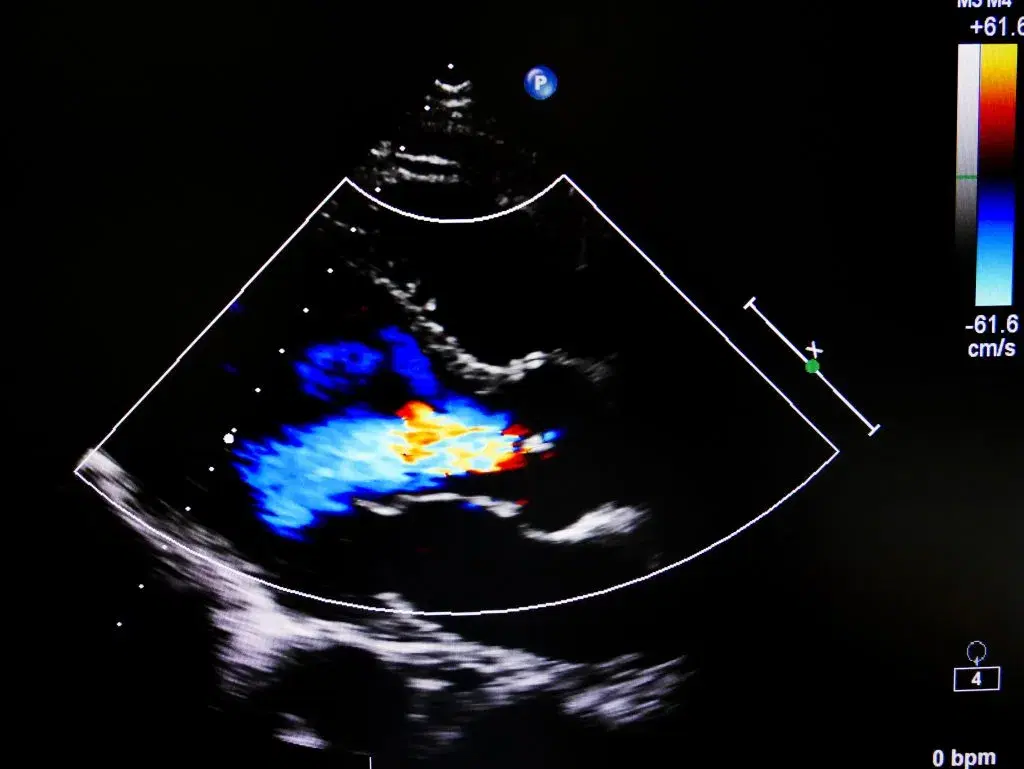

This course covers the causes, symptoms, and treatments of aortic regurgitation, focusing on echocardiography for diagnosis and assessment. Learn surgical and medical interventions for optimal care.

Evaluate proper echocardiographic assessment for accurate diagnosis.

Design diagnostic techniques in echocardiography for assessment of severity.